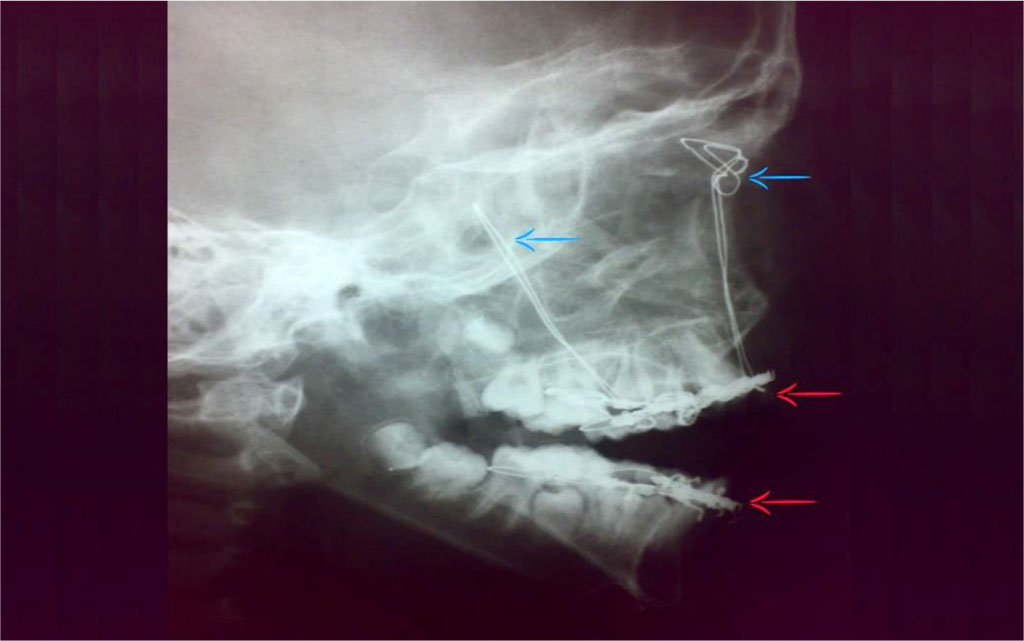

Postoperatively: the patient started oral feeding after three hours; fluids then semisolids. No fever. Pain was controlled by PerfalganTM infusion. Plain skull x-rays (Town and lateral views) revealed proper reduction, optimal mandibular occlusion without any complications e.g., malunion or non-union [Figure 6,7]. The patient was discharged on the fifth day.

Figure 6: Postoperative plain skull x-ray (lateral view); Frontal suspension (blue arrows) and Manduiblo-maxillary fixation (red arrows).